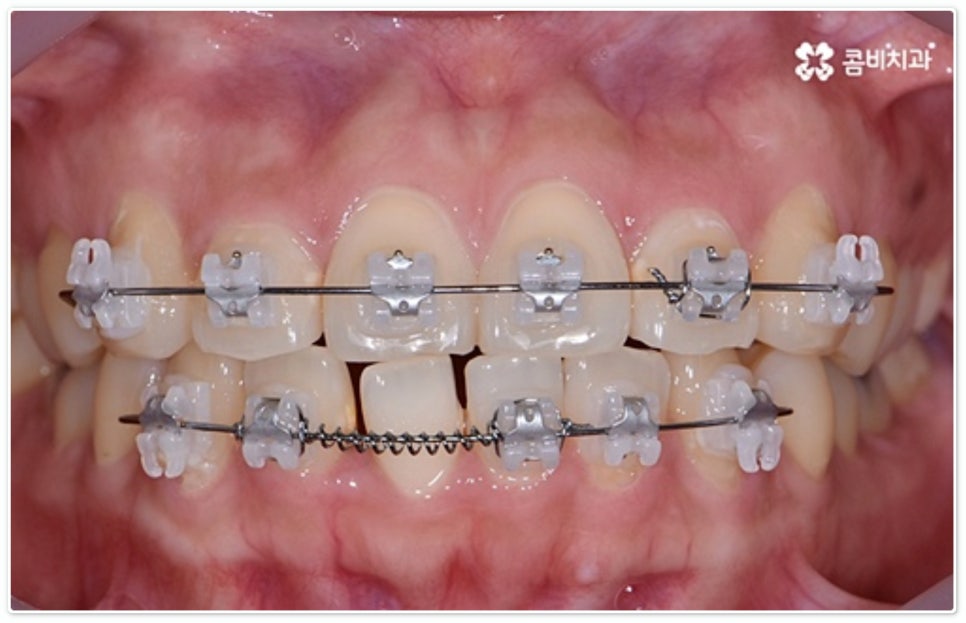

그렇지 않고 전후방 각도 조절 또는 단순 횡적인 움직임으로 치열 개선이 가능한 케이스는 부분 교정을 진행하는데, 사진에서 보시는 사례가 바로 그런 경우에 속하고 있습니다. 앞니 6개에만 브라켓을 부착하였는데 보시다시피 치아 색상과 유사한 세라믹 재질의 장치를 이용하여 심미성 또한 높여 주었음을 알 수 있어요.